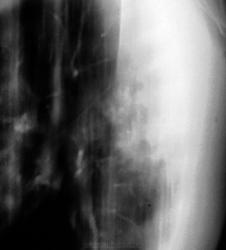

Контроль еще через 1 месяц.

Как умело ваши фтизиатры лечат туберкулез!)).

В облтубе пациента решили прооперировать.

тень овальной формы в подключичном отделе слева туберкулёзной природы. Не исключаю наличие лекарственной устойчивости МБТ к противотуберкулезным препаратам и, как следствие, прогрессирование процесса в лёгких. Возможно, неадекватная терапия? Сочетанная патология в 43 года редкость. Я убежден в правильности тезиса русского клинициста М.Я.Мудрова: "Ищи одну болезнь", который не раз в моей практике подтверждался. На сайте нетипичные случаи демонстрируюся достаточно часто, которые расширяют кругозор многих врачей. Данный случай может попасть в нетипичную группу. Но, так ли окажется? После #22 стало трудно. Буду ждать мнений других участников. Высказвайтесь господа. Сайт бесплатный!

Да, после удаления, верификация - туберкулома.